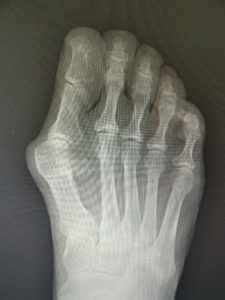

手術前 手術後4年

私は、ミッチェル変法ないしハモンド変法を行います(図6,7)。前日入院、腰椎麻酔(当日のみ臥床となります。)で一時間ほどの手術です。中足骨で骨切りを行い、長さも調節(多くはエジプト型足なので幾分短縮します。)しながら向きを矯正し、骨切り部をワイヤーで固定します。母趾内転筋の切離や、母趾外転筋の移行を検討します。中足骨頭部の種子骨を、正しい位置に戻して縫合します。術後は念のため、3週間ほど短いソックス型のギプスを装着しますが、術翌日から歩行訓練などの理学療法を行います。1ヵ月半ほどで骨癒合します。骨癒合が得られなかった症例はありません。2~3か月で普通に靴が履けます。入院期間は相談して決めればよいのですが、最短なら抜糸まで10日間、或いはギプス固定期間の3週間などが目安となります。

(図6)

手術前 手術後

(図7)

真田理事長による手術の様子。外反母趾|症例 (左から 手術前、手術後、ワイヤ抜去後)